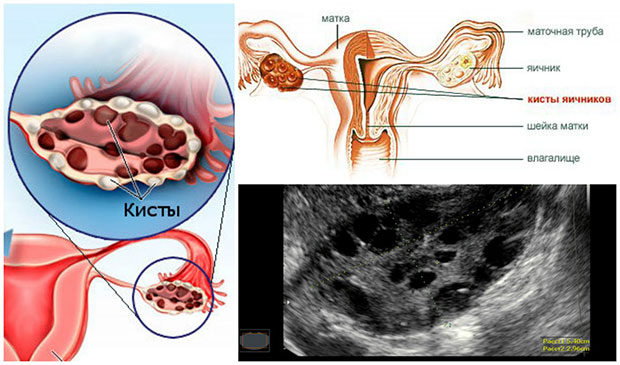

Поликистоз яичников, или синдром склерополикистозных яичников – это название довольно распространенного недуга. По статистике поражает он до 8% представительниц прекрасной половины.

Предшествует ему, как правило, нейрообменный сбой, а также нарушение синтеза эстрогенов и андрогенов, в результате которого на поверхности яичников и возникают многочисленные кисты (на фото). В этом случае яйцеклетка уже неспособна выйти из фолликула. Стоит ли говорить о том, что о беременности здесь и речи быть не может.

При диагностике в расчет берутся данные лабораторных тестов и УЗИ. При этом существует три признака недуга, но окончательный диагноз ставится даже на основании двух.

Речь идет о:

- повышенном уровне андрогенов в крови;

- наличии олиго- или ановуляционного цикла, которые подтверждаются результатами измерения базальной температуры и сбоями в синтезе прогестерона и тестостерона (их показывает анализ крови);

- собственно самих кистах на поверхности яичника.

Почему нельзя диагностировать синдром поликистозных яичников на основании одного УЗИ? Дело в том, что узист может ошибиться и принять обычные физиологические изменения в фолликулах за кисты. Тем не менее, если наблюдается увеличение яичников, подкрепляющееся четким сосудистым рисунком, ошибки, скорее всего, быть не может. Хотя точку в исследованиях все равно ставят биохимические тесты.